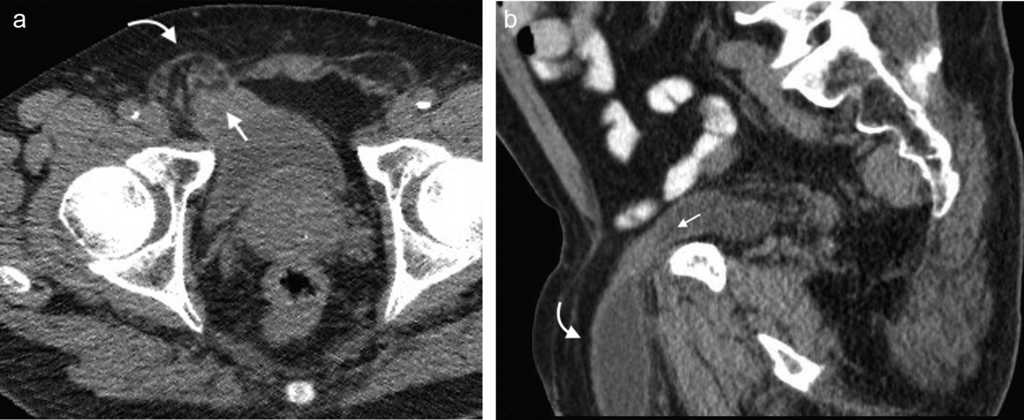

Su diagn??stico cl??nico no es f??cil porque esta hernia se extiende entre las capas musculares o fasciales de la pared abdominal anterior. El orificio herniario puede ser peque??o, dif??cil de localizar y tener grasa omental (fig. 5a), asas de intestino delgado (fig. 5b) o implantes metast??sicos12 (fig. 6).

En su mayor??a estas hernias son adquiridas (espont??neas, postraum??ticas o posoperatorias). Las espont??neas representan aproximadamente el 50% de todas las de la zona lumbar y con mayor frecuencia ocurren en el tri??ngulo superior, con un contenido que puede ser de asas intestinales, grasa retroperitoneal o el ri????n14.

Los s??ntomas suelen ser variables y confusos. Algunas veces la consulta se debe a un dolor lumbar o a una neuralgia posincisional1 (fig. 7).

El contenido est?? relacionado con los diferentes sitios de debilidad de la pared. A nivel epig??strico se encuentra una herniaci??n del antro g??strico, del l??bulo hep??tico izquierdo (fig. 14) o de la ves??cula biliar (fig. 15). Por su parte, dentro de las umbilicales puede haber grasa peritoneal, asas intestinales, implantes metast??sicos (n??dulo de la hermana Mar??a Jos??) (fig. 16) o l??quido asc??tico (fig. 17). En la hernia de Spiegel suele visualizarse grasa y asas intestinales, mientras que las obturatrices muchas veces son descubiertas porque el paciente presenta un cuadro de obstrucci??n intestinal mec??nica que ayuda al diagn??stico. En cuanto a la lumbar, se puede herniar grasa, el polo renal o el l??bulo hep??tico derecho (fig. 18). En el caso de la inguinal, esta tiene un contenido muy variado, aunque la grasa peritoneal y las asas son los m??s frecuentes (fig. 19). Adem??s, puede herniar ??rganos intrapelvianos, como la vejiga (cistocele) (fig. 20) o el ap??ndice (hernia de Amyand)20 (fig. 21), y si se produce la herniaci??n del ap??ndice dentro del canal crural, se denomina hernia De Garengeot9 (fig. 22). Finalmente, en las eventraciones se observan asas de intestino delgado y grueso, ri??ones trasplantados (fig. 23) y vejigas (fig. 24).